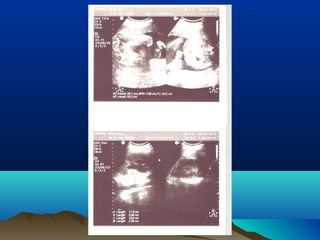

DIAGNOSISDIAGNOSIS

โ€ข ULTRASONOGRAPHY

โ€ข HYDRONEPHROSIS

โ€ข HYDROURETER โ€“ UPPER / LOWER

โ€ข CALCULI โ€“ RENAL / PUJ / URETER

โ€ข PARENCHYMAL THICKNESS

โ€ข URETERIC JET

โ€ข RENAL RESISTIVE INDEX